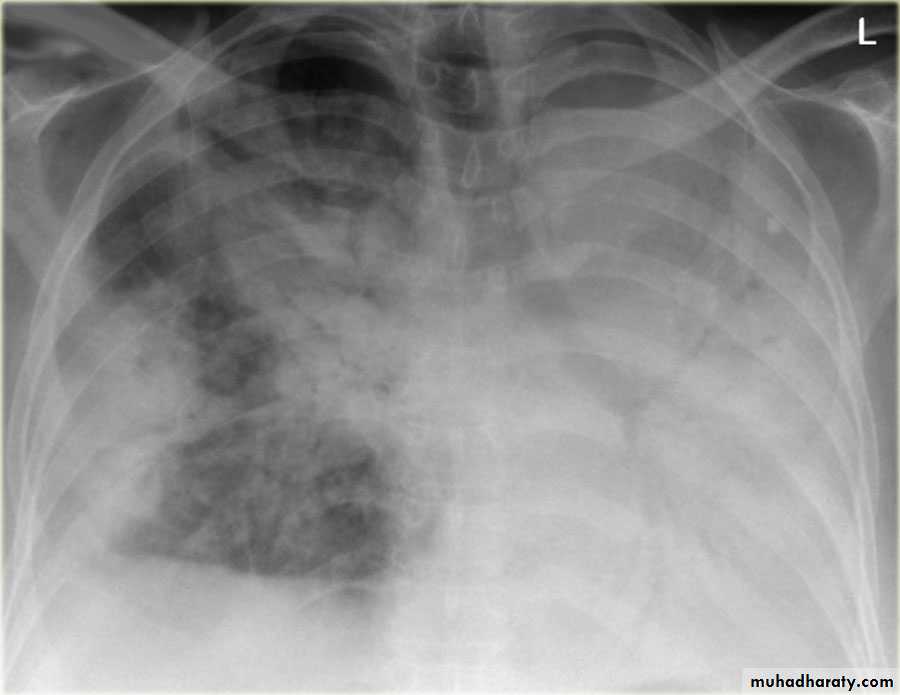

Patient with fever, rigor and dyspnea

Empyema

Differential diagnosis?